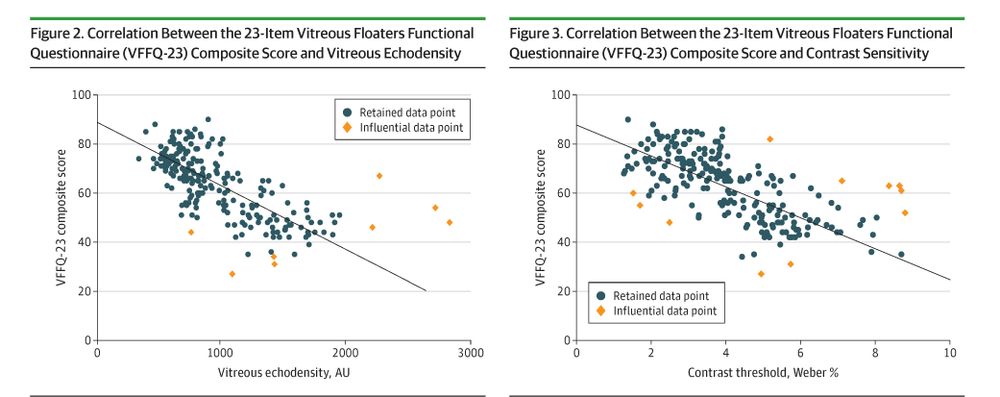

ja.ma/3MoVRX9

ja.ma/3MoVRX9

ja.ma/49GVIIn

ja.ma/49GVIIn